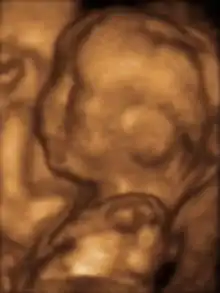

3D ultrasound of ۳-اینچ (۷۶-میلیمتر) fetus (about 14 weeks gestational age)